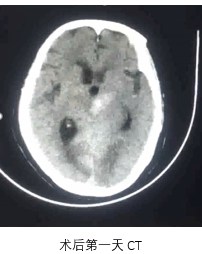

病历夹什么径技·第151期|串联营病历夹:京广连营_https://www.jmylbn.com_新闻资讯_第30张

病历夹什么径技·第151期|串联营病历夹:京广连营_https://www.jmylbn.com_新闻资讯_第31张

病历夹什么径技·第151期|串联营病历夹:京广连营_https://www.jmylbn.com_新闻资讯_第32张

病历夹什么径技·第151期|串联营病历夹:京广连营_https://www.jmylbn.com_新闻资讯_第33张

• 术后即刻:去碘CT排除出血风险,梗死灶出现。

• 术后一天:DWI显示梗塞面积没有明显增大,MRA提示血管再通,发现存在LMCA动脉瘤。

• 术后四天:CT显示没有出血表现,梗死灶已经形成。

• 术后3个月:复查CT显示恢复情况良好。